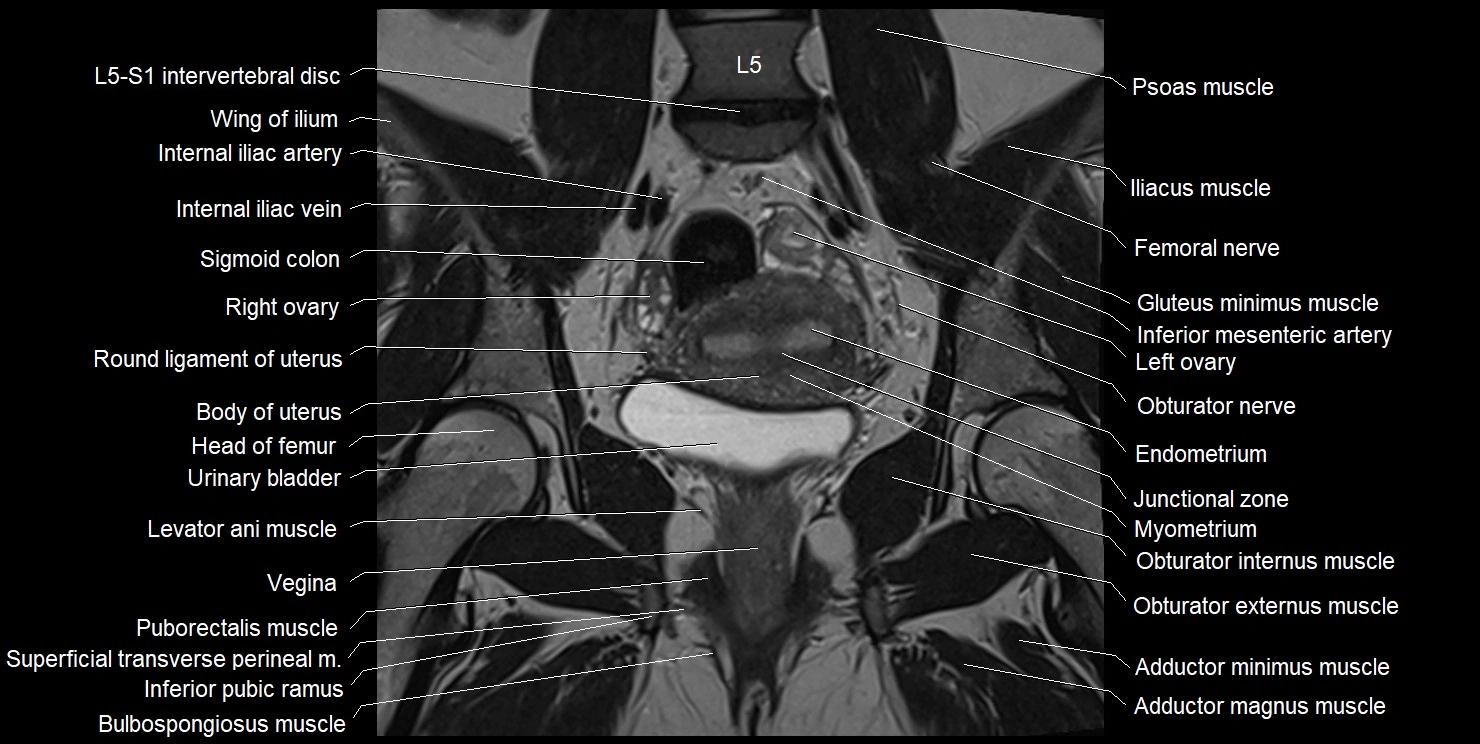

- Body of uterus

- Endometrium of uterus

- Junctional zone of uterus

- Left ovary

- Levator ani muscle

- Myometrium of uterus

- Obturator externus muscle

- Obturator internus muscle

- Obturator nerve

- Puborectalis muscle

- Right ovary

- Round ligament of uterus

- Vagina